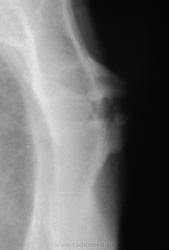

Снимки хорошие, но всё-таки сделал бы томографию. А так, скорее всего, признаки артроза в суставе между телом и рукояткой грудины.

Какой-то остеохондрит типа "Титце".

Артроз то - артрозом, но нет ли тут и асептического некроза нижне-внутреннего края рукоятки грудины....или мне секвестроподобная тень в этом участке "мерещится"?))))

Однако, при таких размеров "шишечке" клиника неблагополучия должна быть!